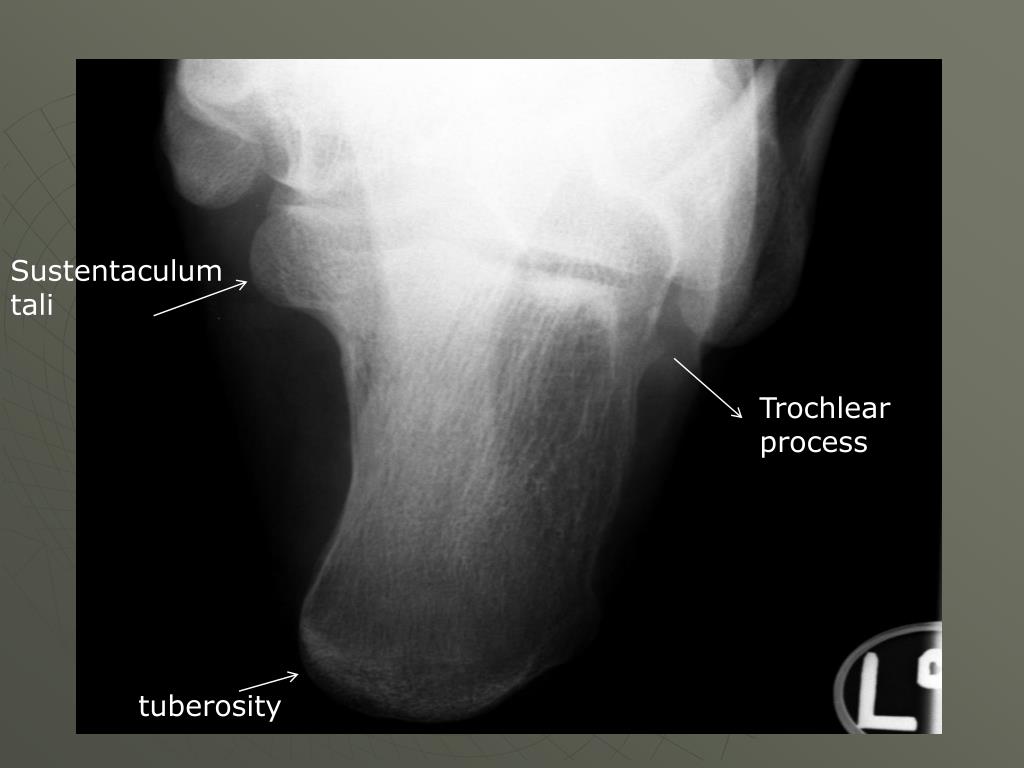

34. Sustentaculum tali Trochlear process tuberosity

35. Structures shown: • An axial projection of the calcaneus ***from the tuberosity to the sustentaculum tali and trochlear process

36. AP Axial Right Calcaneus

37. Check for: • Calcaneus should be visualized to include the talocalcaneal joint • No rotation of calcaneus (check the first or fifth metatarsals) • Density to see joint without burn out of tuberosity (two films if not using DR or CR)

38. Rotation / foot flexion Rotation : can see 4th & 5th metatarsals Too much flexion Can’t see joint space Good

39. Structures shown: • Lateral projection of the ankle joint and the calcaneus and adjacent tarsals.

40. Lateral Left calcaneus

41. Check for: • No rotation of the calcaneus • Density can you see soft tissue and bone • Sinus tarsi seen • Ankle joint and adjacent tarsals should be on the film